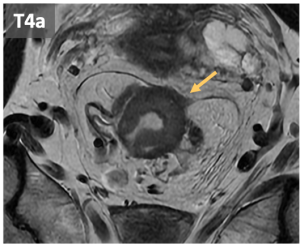

- T4: can be classified in:

- T4a: invasión of adjacent organs

-